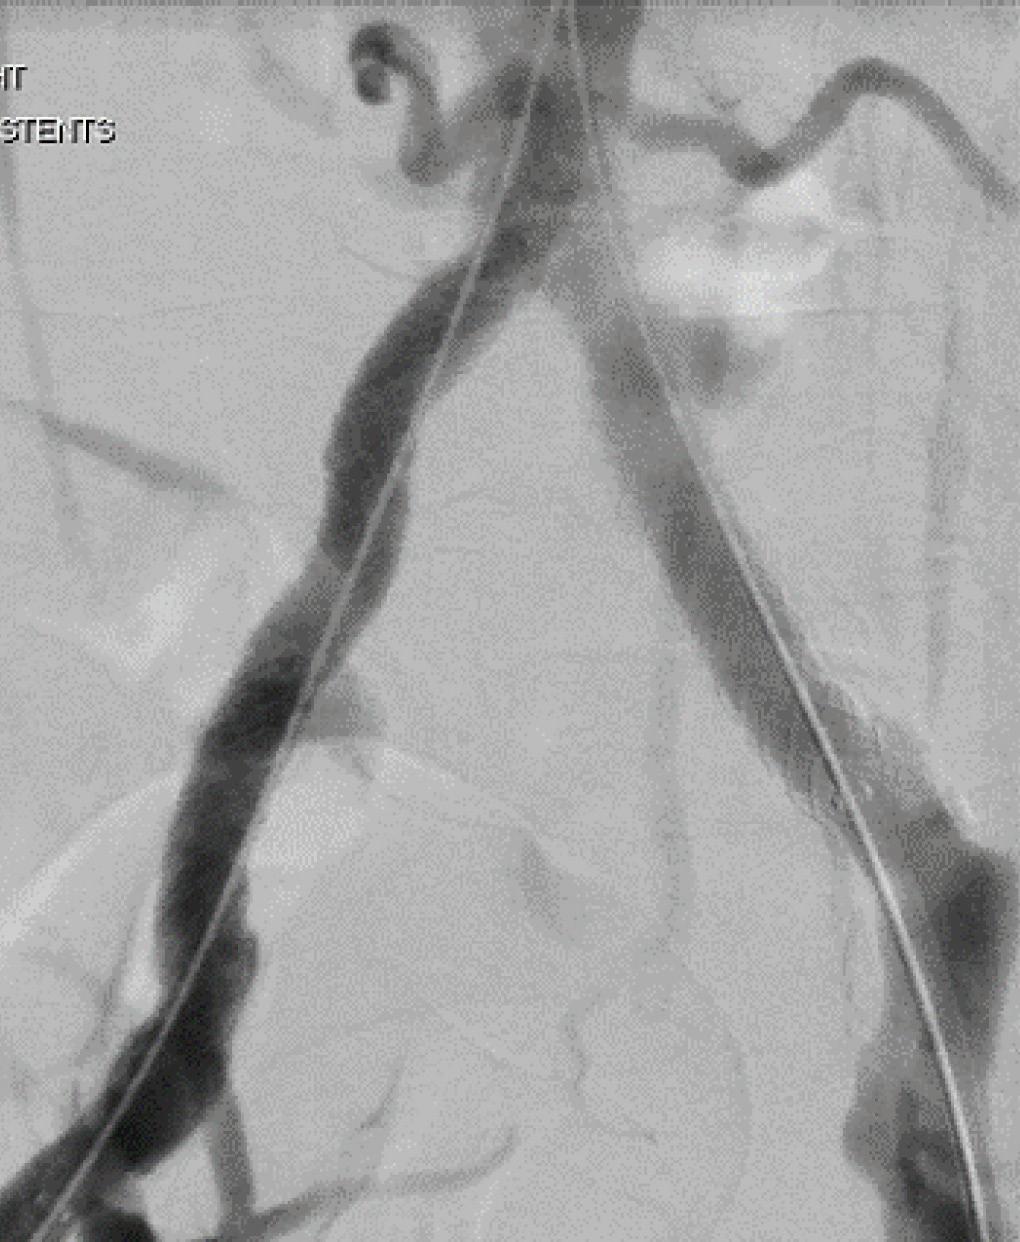

BEST-CLI LOOMS LARGE OVER VAM 2023 PROGRAM

The landmark BEST-CLI randomized-controlled trial (RCT) was featured in multiple scientific and invited sessions dotted across the program in National Harbor.

Two of the headline points of interest—the inaugural Frank J. Veith Distinguished Lecture and a session dedicated to debate and analysis of both BEST-CLI and BASIL-2, another landmark RCT looking at chronic limbthreatening ischemia patients— saw attendees flock to the main plenary hall for a series of talks around the hot topic.

During the Veith lecture, BEST-CLI lead investigators Alik Farber, MD, and Matthew Menard, MD, struck a conciliatory tone as they laid bare the blood, sweat and tears shed on their journey to complete the study. “We hope our story encourages others to pursue their research ambitions, even in the face of obstacles, self-doubt and judgment of others,” Farber told VAM.

“Turf battles in the vascular community have been, and still are distracting, destructive,

highly counter-productive and of very little service to our patients,” added Menard.

During the session addressing both BEST-CLI and BASIL-2 together, Farber and Menard reiterated their message that the former trial “supports a complementary role for open and endovascular revascularization strategies” and the need for expertise in both. The session also heard from BASIL-2 lead investigator Andrew Bradbury, MD, from the University of Birmingham in Solihull, England, who addressed the question of whether the trial would change practice in the UK. He said that in around 50% of patients it is not “obvious” that infrapopliteal vein bypass or best endovascular therapy is preferable.—